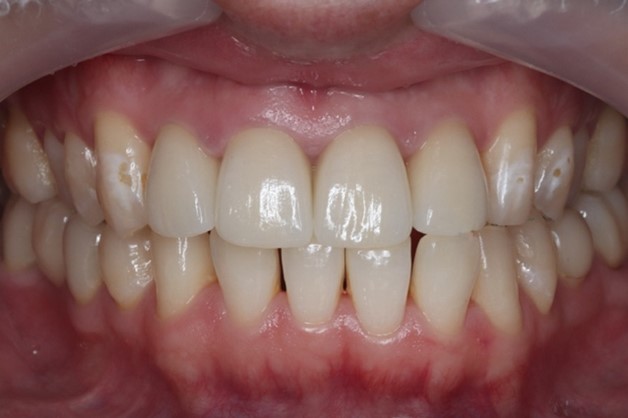

治療後の様子

目白マリア歯科|【症例】自然な美しさを考慮した審美歯科治療|治療後の口腔内写真

歯肉の状態は非常に健康な状態に保たれ、かみ合わせも仮歯製作時と同様に良好です。

今回の患者様は歯と歯茎の境目と、前歯部の色を気にされていました。前歯の詰め物をオールセラミックの材料でやり変えることで、自然で明るい口元を実現しています。